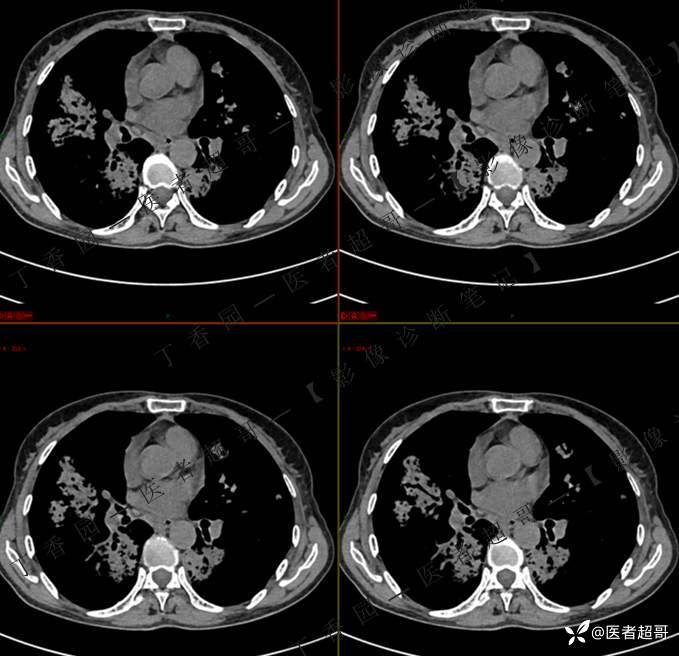

临床治疗一周后复查